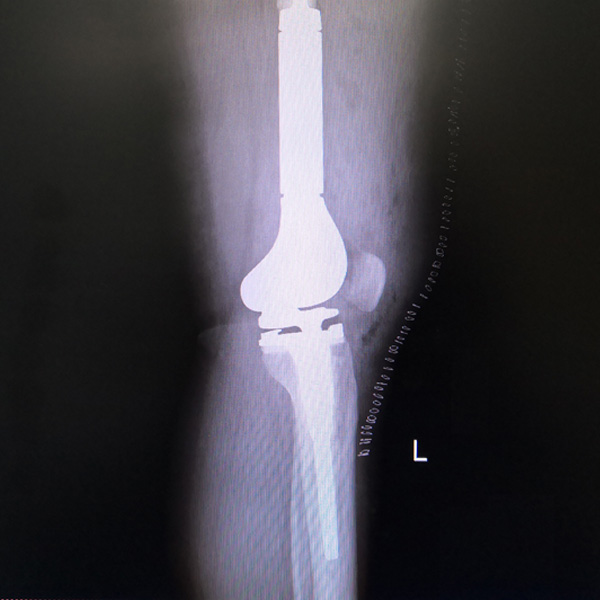

• 骨肉瘤手術骨肉瘤手術手術后手術前

骨肉瘤手術

患者張某,女,14歲,診斷為“左股骨遠端骨肉瘤”,當地醫院因為醫療技術和能力的限制,只能考慮截肢手術。患者家屬通過平臺推薦,指定到哈......

• 膝關節內翻膝關節內翻手術后手術前

膝關節內翻

患者劉某某,女66歲,左側膝關節嚴重內翻(俗稱的“羅圈腿”),疼痛到不能生活自理。經平臺推薦到哈爾濱醫科大學附屬第二醫院骨關節科就診,......